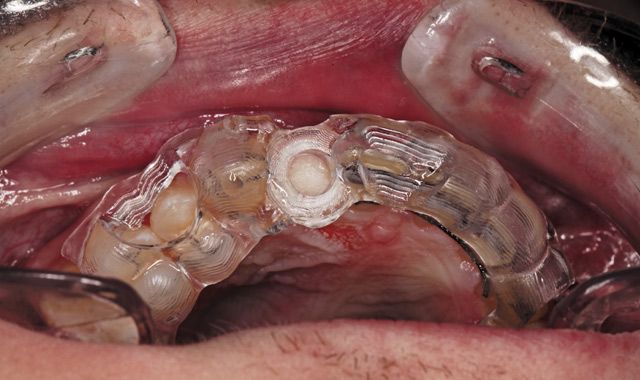

Fig. 23 The clinically seated surgical guide for guided surgery.